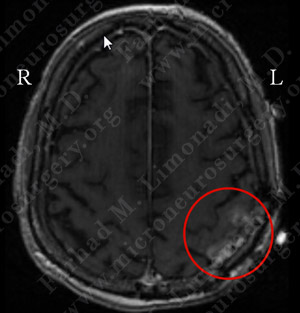

Imaging

Computer navigation and stereotaxy utilized to map and localize the tumor (outlined in yellow) during surgery.